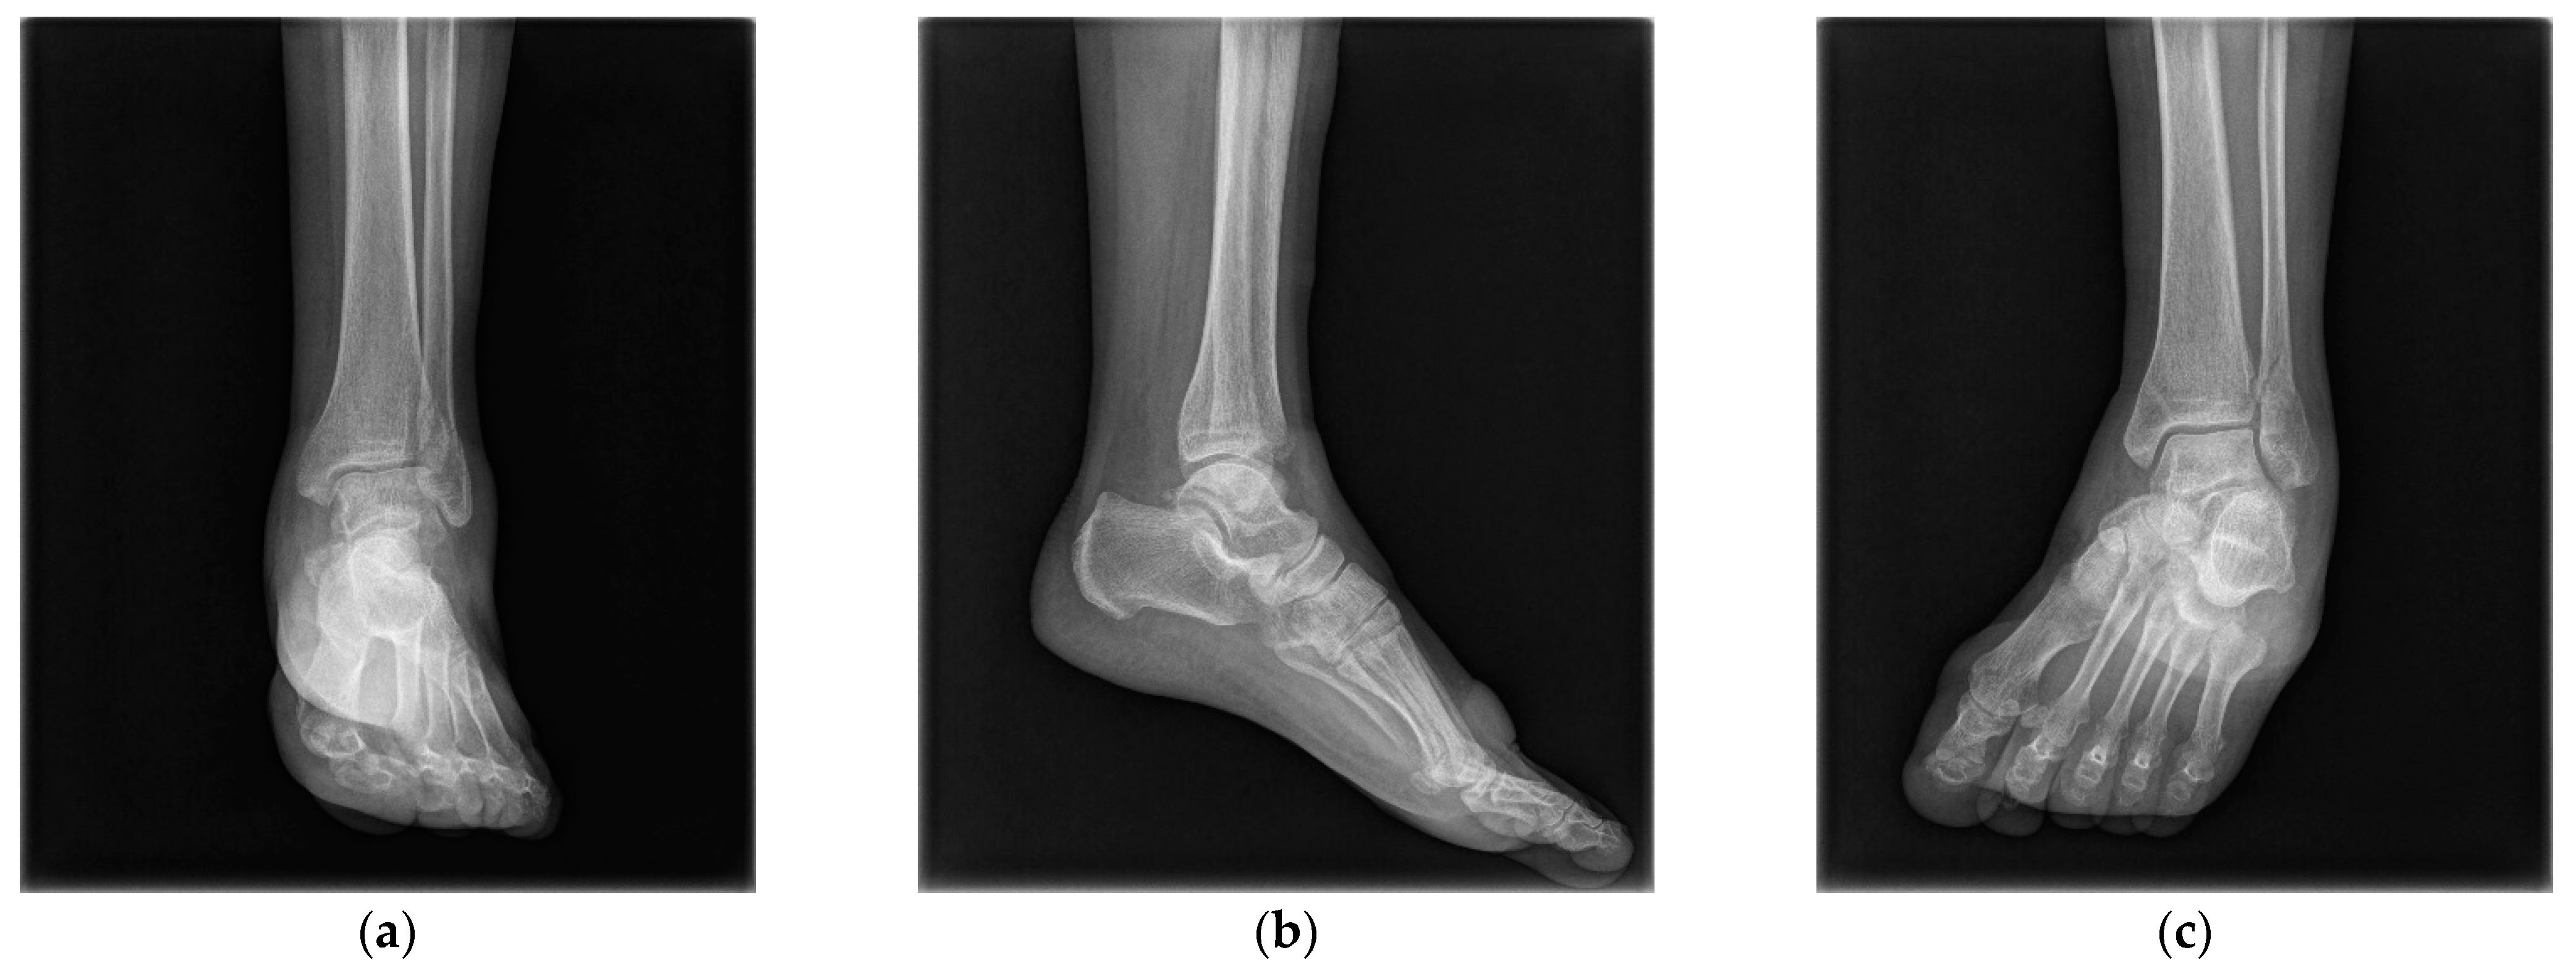

2.3. Radiological Evaluations